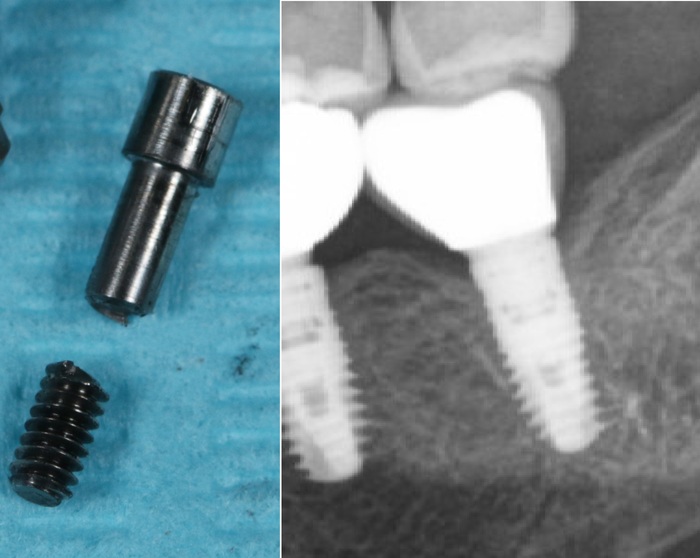

Часть с резьбой осталась в имплантате

На рентгеновском снимке:

Внутренний конструктив имплантата:

Благо я работаю с профессионалами. Иван Алгазин, наш ортопед, умудрился достать обломок винта, что крайне сложно сделать не повредив принимающую часть в имлпантате:

На фото ниже виден шестигранник, обратите внимание какой он шероховатый. Он должен быть отполированным, гладким. (К слову, о той микроподвижности, про которую я говорил выше)

Сравнение абатмента из кобальт-хрома и титана: